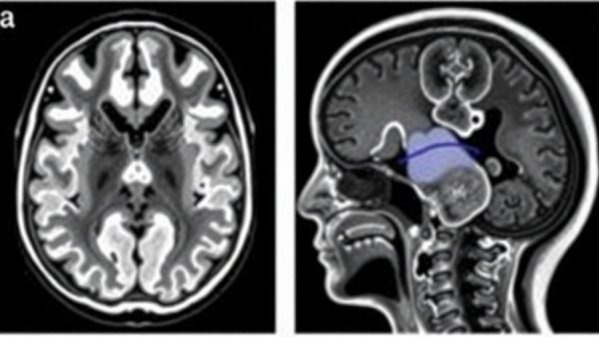

Congenital abnormalities in the brain and spine can take many forms, including neural tube defects such as spina bifida and Chiari malformations. Chiari malformation occurs when parts of the brain excessively descend into the spinal canal, potentially impairing cerebrospinal fluid flow and leading to other complications, including hydrocephalus. A critical understanding of what these malformations entail can empower concierge practice owners to better inform patients about warning signs and promote beneficial prenatal care.

Diagnosing these conditions typically involves imaging techniques such as MRI or ultrasound, which offer detailed insights into the brain's structure and functionality. Early detection is essential, as it allows for timely interventions that can minimize long-term effects on a child's cognitive and motor skills. Pediatricians and neurologists collaborate closely to evaluate and recommend treatment, often involving a multidisciplinary team for optimal management.